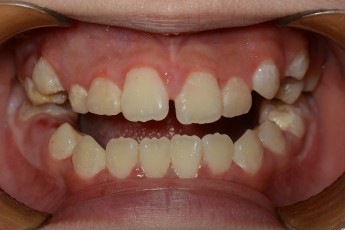

BEFORE & AFTER

- 덧니교정